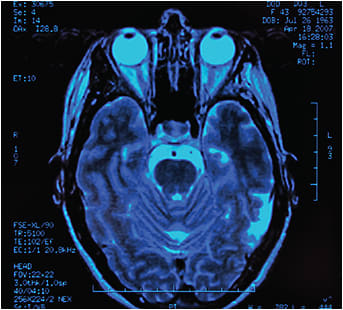

Patients with acute symptoms such as headache or visual loss may require immediate brain imaging or other tests.